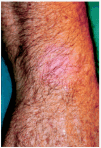

Los 5 pacientes presentaron curación clínica a las 8 semanas de finalizar el tratamiento (tabla 1). La biopsia postratamiento realizada a tres de ellos demostró la curación histológica. Las figuras corresponden a las lesiones antes y después del tratamiento del paciente 3 (figs. 1 y 2) y del paciente 4 (figs. 3 y 4).

Fig. 3.--Paciente 4, antes de iniciar el tratamiento.

Fig. 4.--Paciente 4, a las 8 semanas de finalizar el tratamiento.